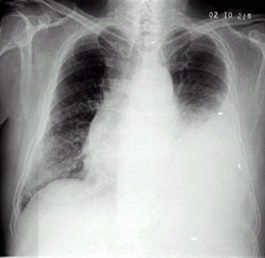

02卷-5.女性,55岁,胸闷、气短5天,加重1天。诊断(本题满分2.00分)

A.右上肺炎

B.左侧胸腔积液

C.左下肺不张

D.左肺癌

本题答案:B

题目解析:【该题针对“X线-胸腔积液”知识点进行考核】